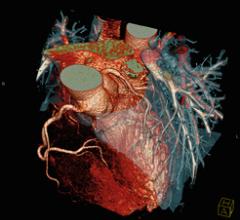

June 27, 2011 — Researchers may have discovered one reason that African-Americans are at increased risk for heart attacks and other cardiovascular events.